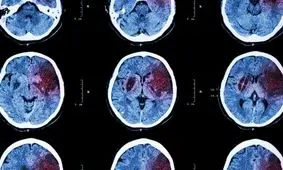

پزشکان میگویند با «انتخاب سبک زندگی سالم و کنترل عوامل خطر» میتوان از بروز سکته مغزی پیشگیری کرد.